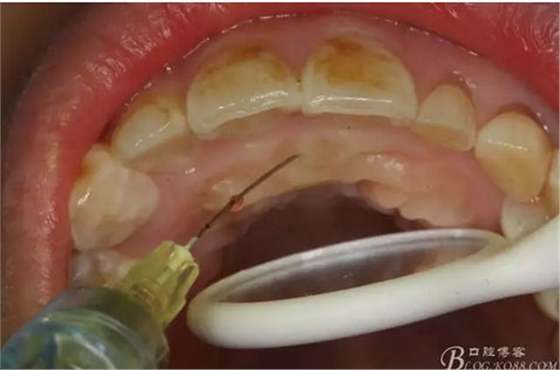

圖4.唇側(cè)局部浸潤麻醉。注意要多點浸潤麻醉。

圖5.腭側(cè)局部多點浸潤麻醉。粘膜發(fā)白即可。